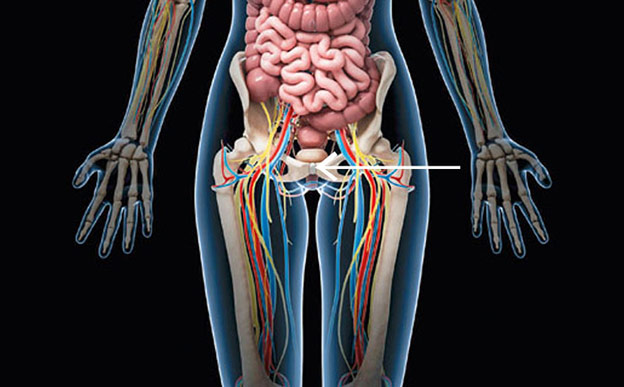

El vello púbico

La evolución eliminó casi todo nuestro vello corporal, pero lo mantuvo en el pubis para protegernos de heridas e infecciones. Sin embargo, la moda de la depilación púbica –informa la Asociación Española de Dermatología– ha provocado un aumento alarmante de las enfermedades de transmisión sexual entre los jóvenes, sobre todo los condilomas genitales causados por el VPH. Por un lado, se debe a los contagios piel con piel; por otro, las heridas de la rasuración facilitan que los patógenos penetren e infecten de herpes, impétigos o sífilis.